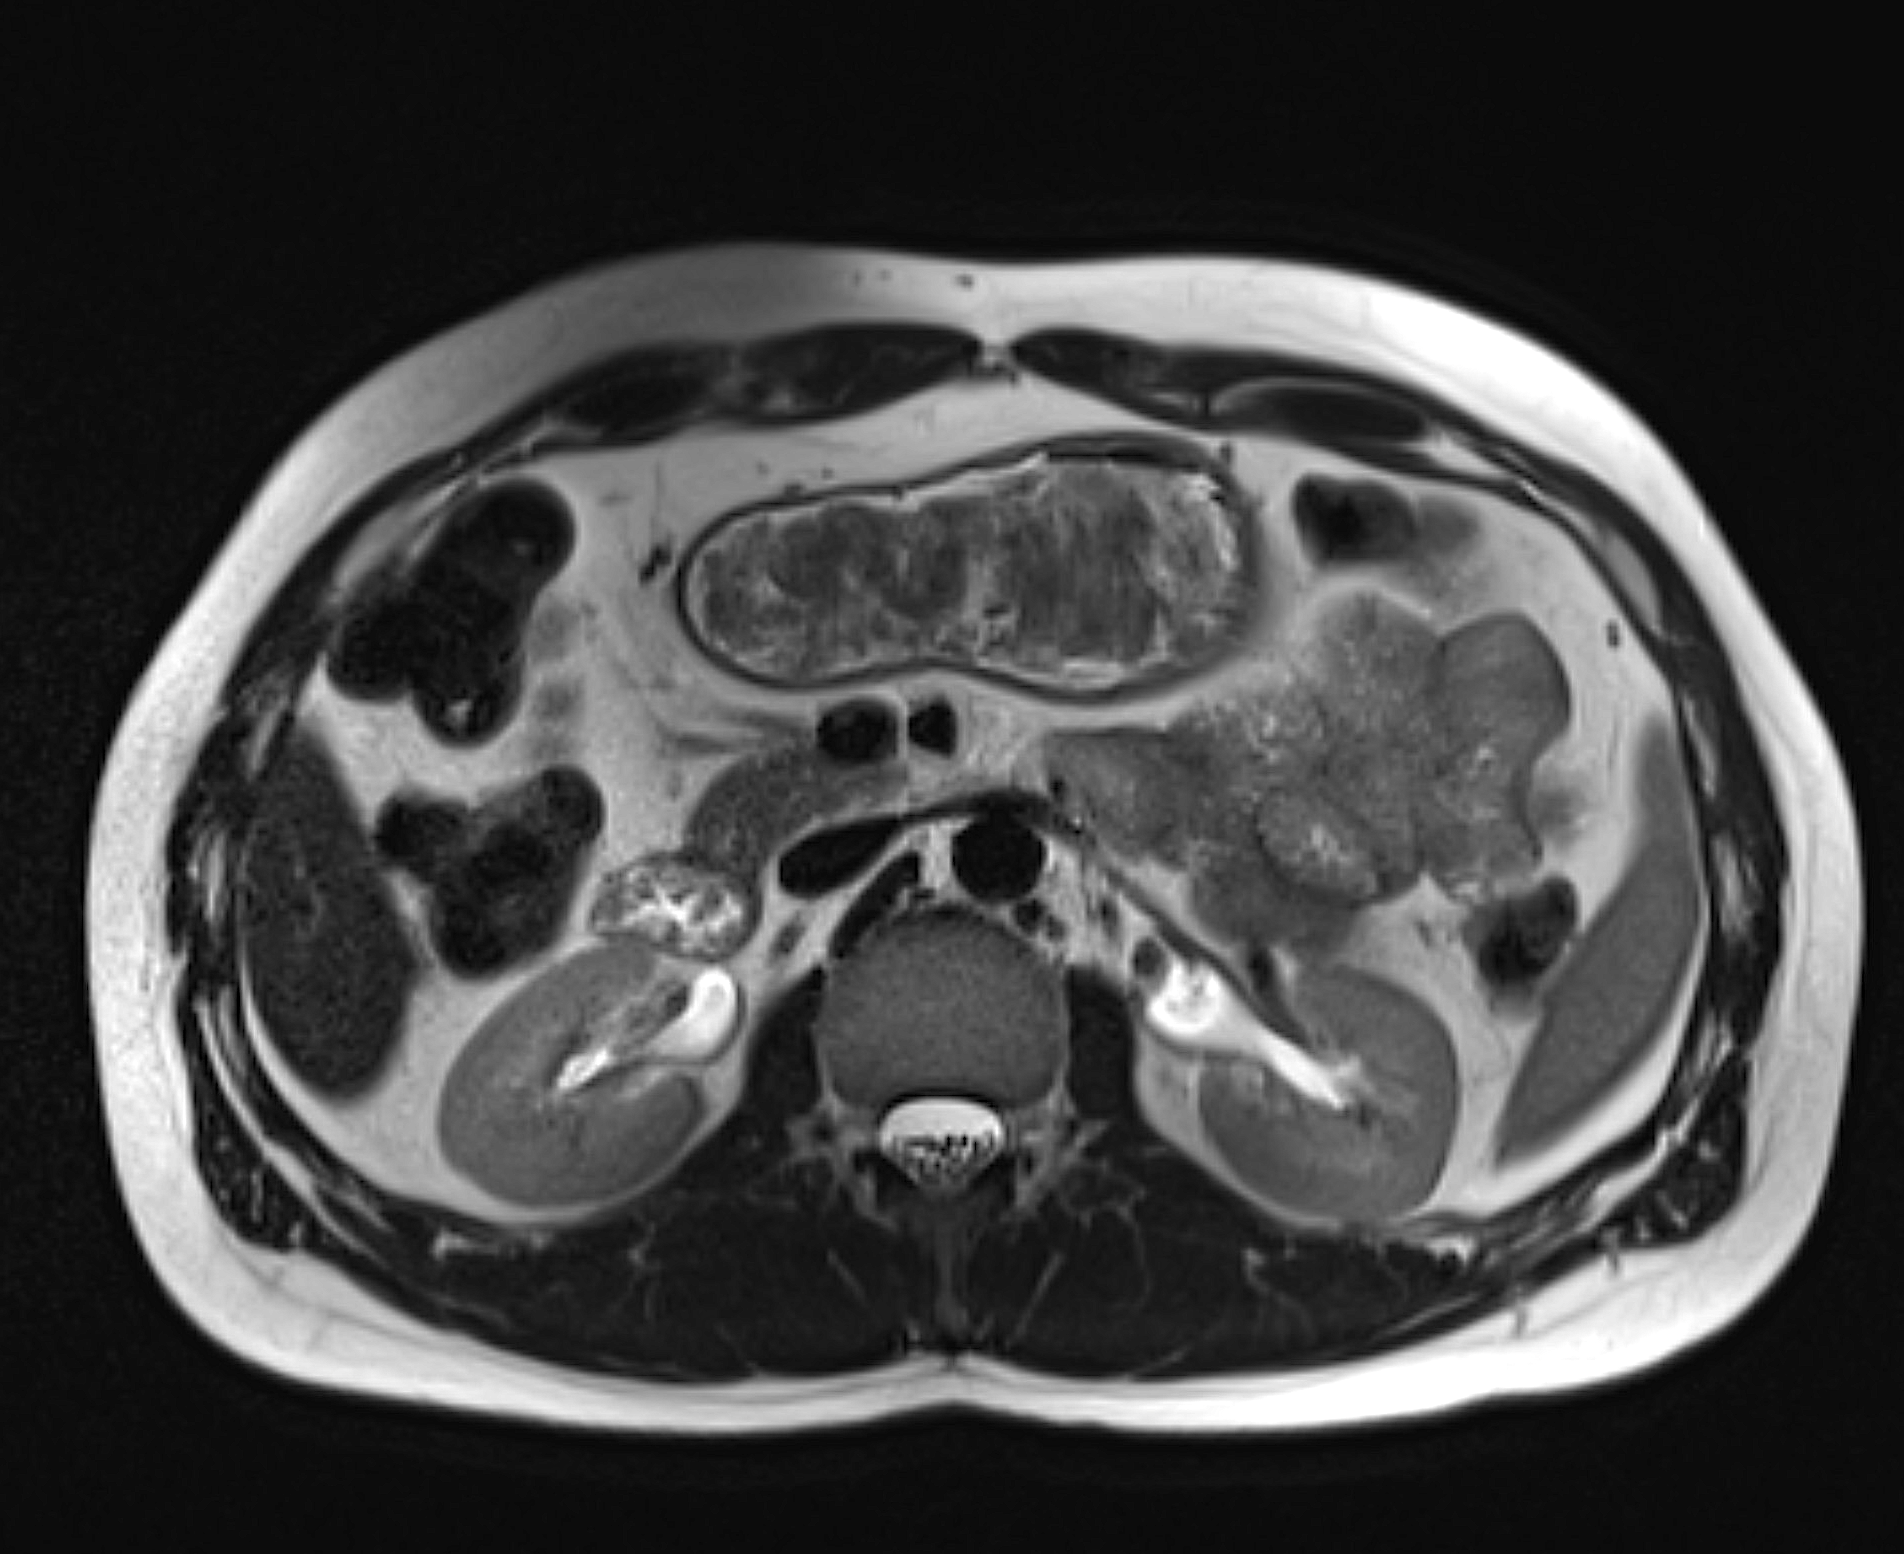

MRI is often used when the following conditions in the kidneys are suspected

- Kidney cancer or tumor in the renal pelvis

- Simple or complex kidney cysts

- Hydronephrosis (fluid accumulation due to outflow obstruction)

- Urinary tract stones (stones) in the upper urinary tract

- Pyelonephritis or other inflammation of the kidney

- Changes after surgery or transplantation